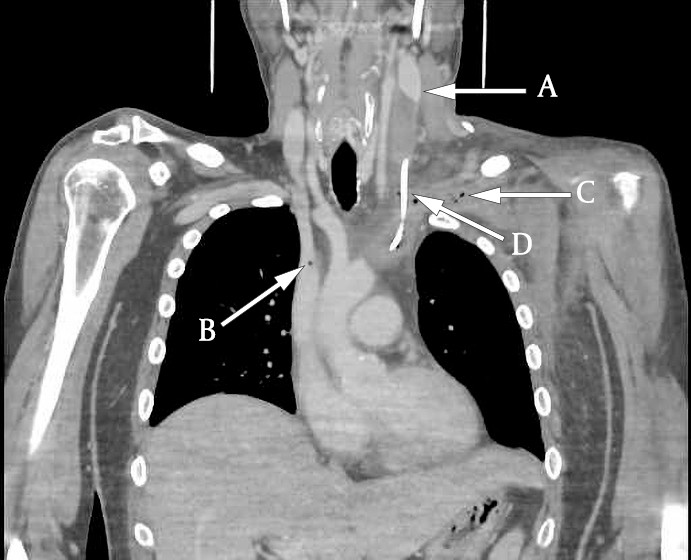

Ultralydundersøkelsen av halsen viste imidlertid en betydelig trombemasse som nærmest totalokkluderte venstre v. jugularis interna og v. subclavia (figur 1 og 2). Den totale utbredelsen av tromben kunne ikke fremstilles med ultralyd, og det ble derfor supplert med en CT-venografi, som viste utbredt trombosering som omfattet nedre del av venstre v. jugularis (fra nivå med carotisbifurkaturen), v. subclavia og v. brachiocephalica frem til innløpet av v. cava superior (figur 3). Det var multiple luftbobler fordelt i trombemassen. Vi mistenkte at dette var forårsaket av bakterier, og dermed at en infisert trombe var fokus for pasientens infeksjon.

Ultralyd er en ikke-invasiv og kostnadseffektiv metode for å påvise trombemasser. Dessverre er den suboptimal for diagnostikk av tromber lokalisert dypt under mandibula eller clavicula. CT-venografi er derfor av mange anbefalt som foretrukket undersøkelsesmetode (6). I vårt tilfelle fikk vi med CT-venografi identifisert hele utbredelsen av trombemassen samt påvist karakteristiske luftbobler som underbygget mistanken om infisert trombe.

Funn av små intravenøse luftbobler på CT er ikke unormalt, da små luftbobler kan bli injisert sammen med kontrastvæsken. Luftbobler kan også sees i det mesenterielle eller portalvenøse systemet grunnet iskemi eller infeksjon. Luftbobler inne i en trombemasse er derimot sjeldent, og funnet forsterker derfor mistanken om infisert trombe (7).